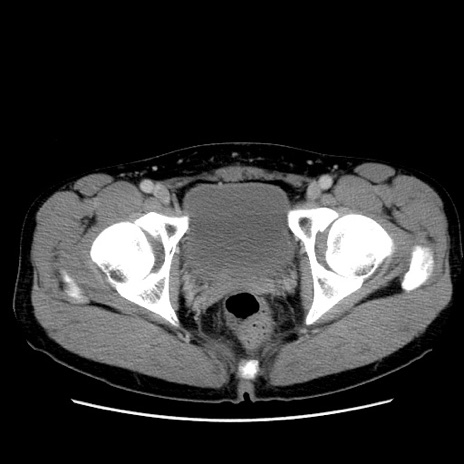

冠状断像

【症例】20歳代 男性

【主訴】心窩部痛

【現病歴】今朝より上腹部痛あり。一旦軽快していたが再度出現したため救急要請。昨日夕に白身の魚を含む刺身を食べた。

【身体所見】BP 136/89mmHg、HR 74/min、BT 37.0℃、腹部:膨満、軟、心窩部に圧痛あり。反跳痛なし、筋性防御なし、腸雑音やや亢進あり。

【データ】WBC 17700、CRP 0.48